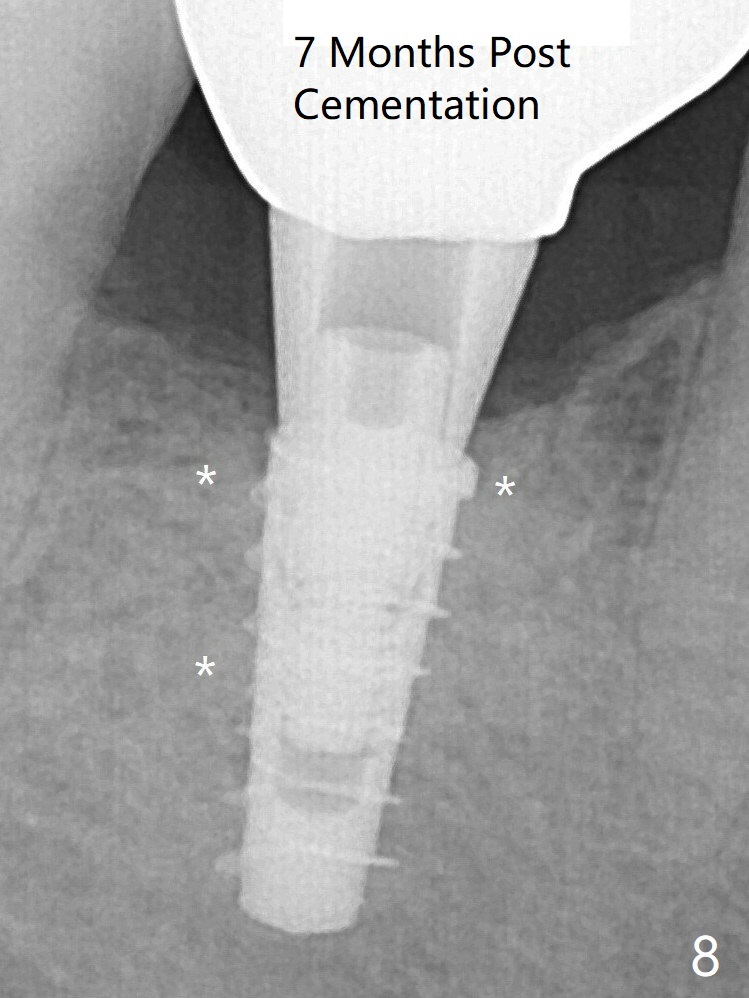

For safety, a 4x9 mm IBS implant is placed with insertion torque 40 Ncm; a 5x5.7(4) mm abutment is immediately placed for an immediate provisional to cover the large socket and keep Vera graft in place (Fig.4 *). Yellow dashed line: apical osteotomy; red dashed line: Mental Loop. Impression is taken nearly 3 months postop (Fig.6). The bone density around the implant increases 7 months post cementation (Fig.8 *). The higher density bone seems to extend coronally 1 year 7 months post cementation (Fig.9). The dense bone apparently extends toward the abutment as well 3 years 5 months post cementation (Fig.10 curved arrows).